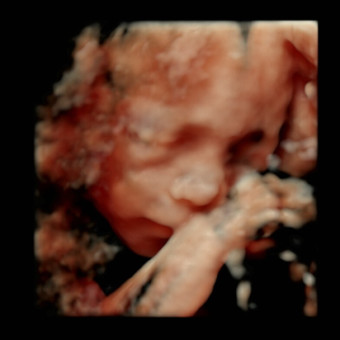

Amber's Baby Registry

Amber Culley & Jonathan Barco

July 2026